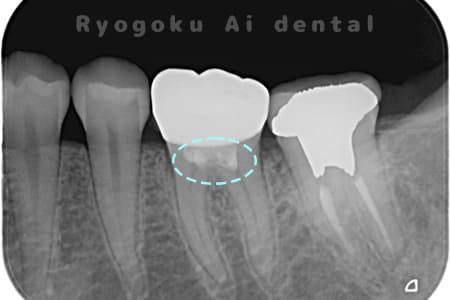

Case08

-

- 原因

- 重度カリエス

- 治療内容

- 断髄治療

- 治療回数

- 1回

- 治療費用

- 66,000円

右下に違和感があるとのこでご来院。レントゲンでも神経に達する虫歯があり、神経の保存を行う断髄治療について説明し、同意を得て行いました。特に知覚過敏症状もなく、神経の反応も良好なため、今後は定期検診にて経過を追っていくこととなりました。

<リスク・副作用>

術後は痛み、腫れ、痺れなどの副作用が生じる場合があります。症状が再発する可能性があります。その場合は抜髄する必要があります。